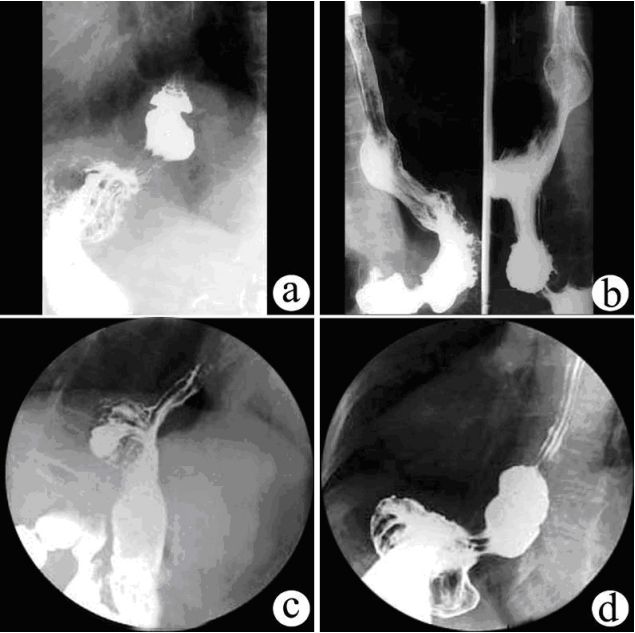

食管裂孔疝:膈上疝囊。

食管裂孔疝有4种:短食管型、食管旁型、混合型、滑动型,每型都有不同的表现,但最直接的还是膈上疝囊。

食管裂孔疝的造影检查分别如下:

短食管型食管裂孔疝

短食管型食管裂孔疝(不可回复性)

不可复性食管裂孔疝

滑动型食管裂孔疝

食管旁型食管裂孔疝

可能你觉得这些图像太多,使得记忆分散,下面一张图包含了4种食管裂孔疝。